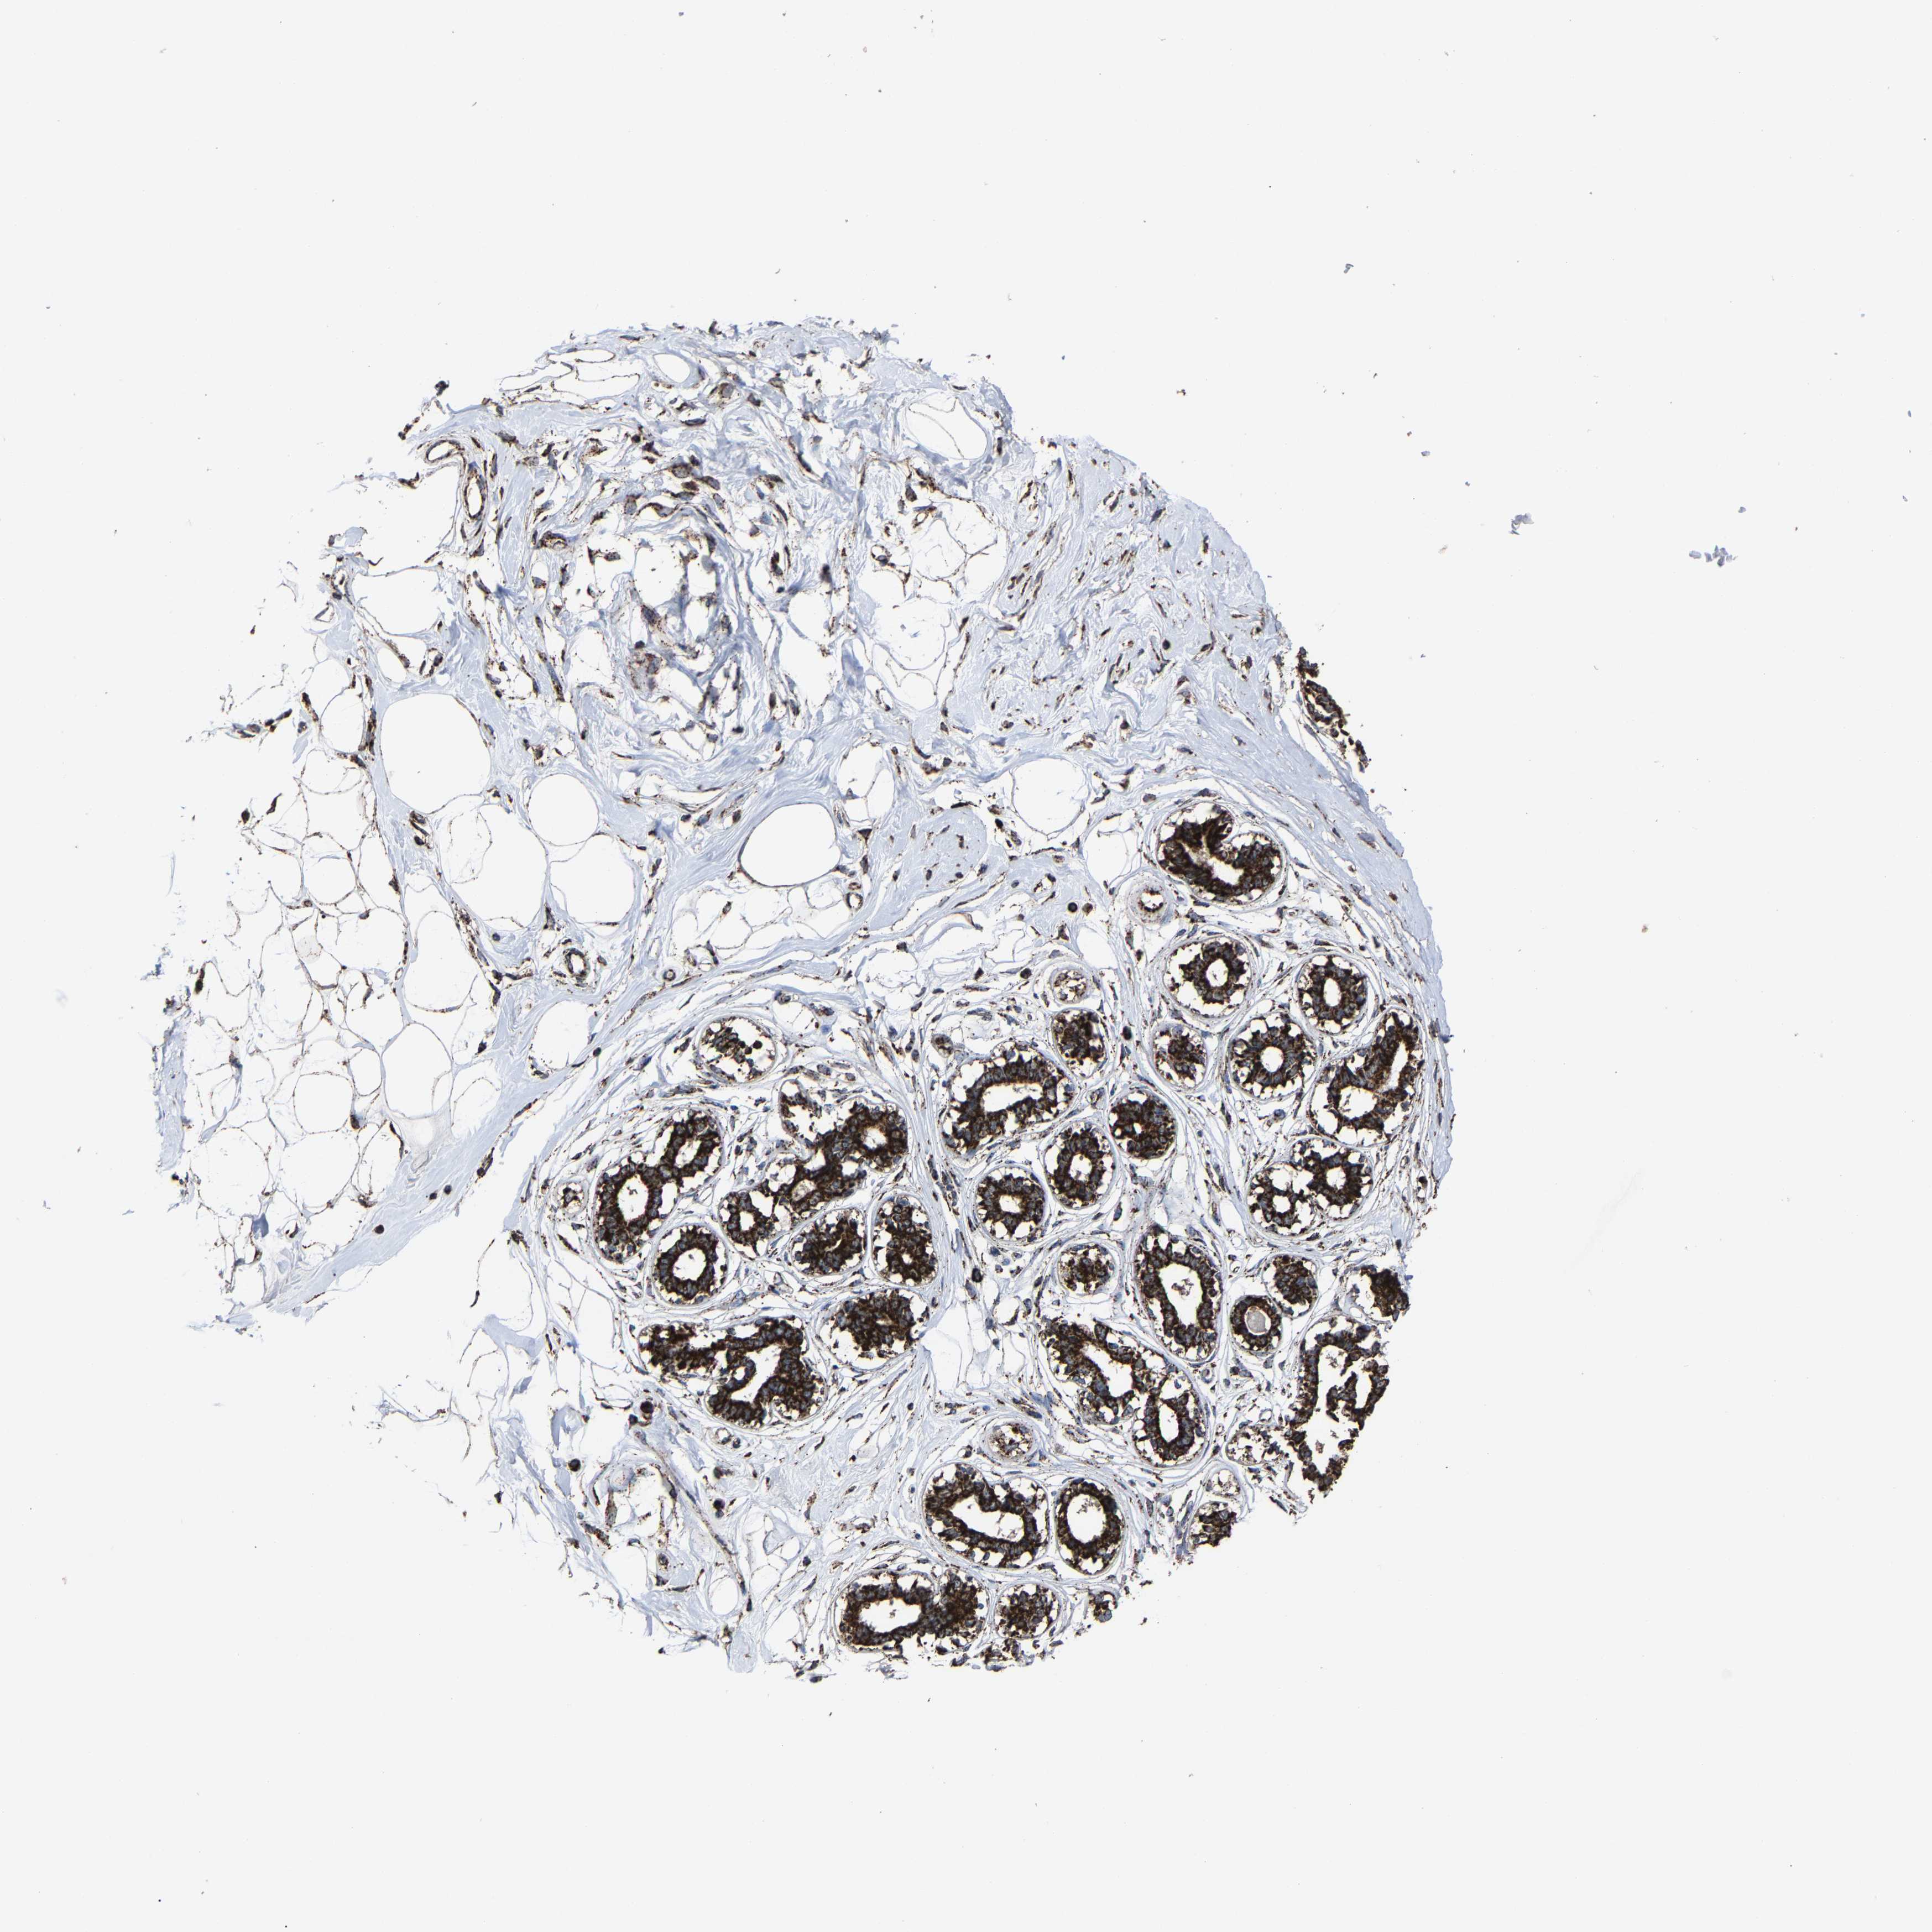

BREAST - Antibody stainingi

Antibody staining in the annotated cell types in the current human tissue is reported as not detected, low, medium, or high, based on conventional immunohistochemistry profiling in selected tissues. This score is based on the combination of the staining intensity and fraction of stained cells.

Each image is clickable and will lead to virtual microscopy that enables deeper exploration of all samples and also displays staining intensity scores, fraction scores and subcellular localization as well as patient and tissue information for each sample.

Antibody HPA019791Antibody HPA020463Antibody HPA030427Antibody CAB034142

Adipocytes MediumMediumLowLow

Glandular cells HighHighMediumHigh

Myoepithelial cells HighHighMediumHigh